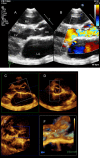

This review article will guide the reader through the basics of echocardiographic assessment of congenital left to right shunts in both paediatric and adult age groups. After reading this article, the reader will understand the pathology and clinical presentation of atrial septal defects (ASDs), ventricular septal defects (VSDs), atrioventricular septal defects (AVSDs) and patent arterial duct. Echocardiography is the mainstay in diagnosis and follow-up assessment of patients with congenital heart disease. This article will therefore describe the echocardiographic appearances of each lesion, and point the reader towards specific features to look for echocardiographically.